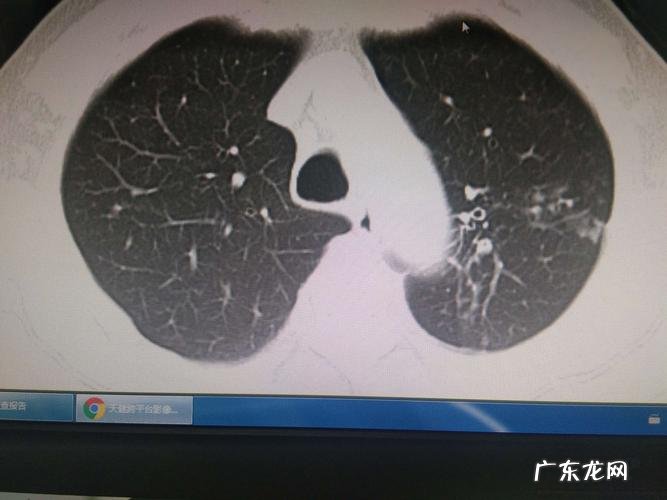

【干咳无痰是肺结核吗 肺结核没痰是好事吗】首先,你的胸痛是一种常见的现象,也是正常的 。其次,许多患者在停止服药后仍会出现胸痛 。这是由于胸膜粗糙引起的,但胸痛会逐渐消失 。咳嗽痰不一定是结核病,结核病患者咳嗽明显,但咳痰少,多为少量白粘痰,常伴有痰血现象,只有当结核病患者合并细菌感染时,咳嗽痰量才会显著增加 。然而,结核病患者也有明显的结核病中毒症状,如下午低热、盗汗、瘦、差、疲劳等不适,结核病的诊断也需要根据胸部影像学和痰培养进行诊断 。咳嗽痰也可能是由下呼吸道传染病引起的,如肺炎、肺脓肿和支气管扩张 。因此,咳嗽痰多为排外是否存在肺结核,患者需要根据临床症状、胸部影像学检查和相应的痰检查 。